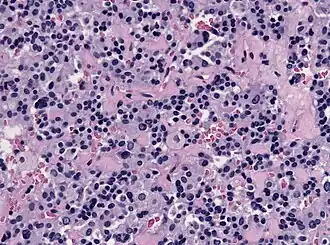

Thyrotropes appear basophilic in histological preparations. In the image displayed on the right, thyrotropes are the cells with the bluish-purple cytoplasm and the dark purple nucleus. Normal morphology of these cells is characterized by a round shape. However, these cells are best displayed under light microscopy performed following immunohistochemistry with TSH. This specific type of imaging allows for the visualization of the location of thyrotrophs in the anterior pituitary gland. Thyrotropic cells are clustered together in the anteromedial region of the gland.[3]

This image shows the histology of a thyrotroph tumor. These thyrotroph tumors are referred to as thyrotroph adenomas, and are very rare. They typically present as functional macroadenomas and generally appear in individuals in their 50s. Thyrotroph adenomas are not well understood as they only comprise roughly 1% of all pituitary tumors.[9] These tumors typically result in increased secretion of TSH. Individuals with thyrotroph adenomas typically have hyperthyroidism and diffuse goitre. Diffuse goitre refers to the elongated enlargement of the thyroid gland that results from the increased expression of TSH.[10]

In histological staining, the thyrotropic cells appear more elongated and spindle shaped and are regularly accompanied by fibrosis.[9]